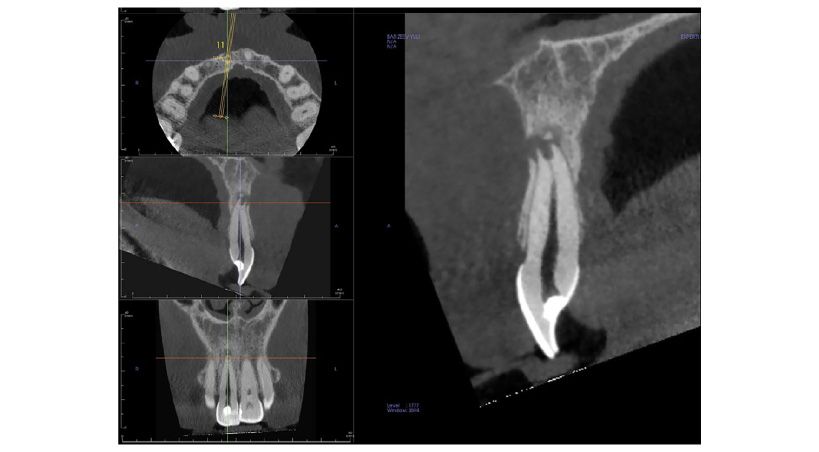

Retratamiento y restauración estética de incisivo superior con conducto radicular calcificado mediante un sistema de navegación dinámica

Reporte de un caso